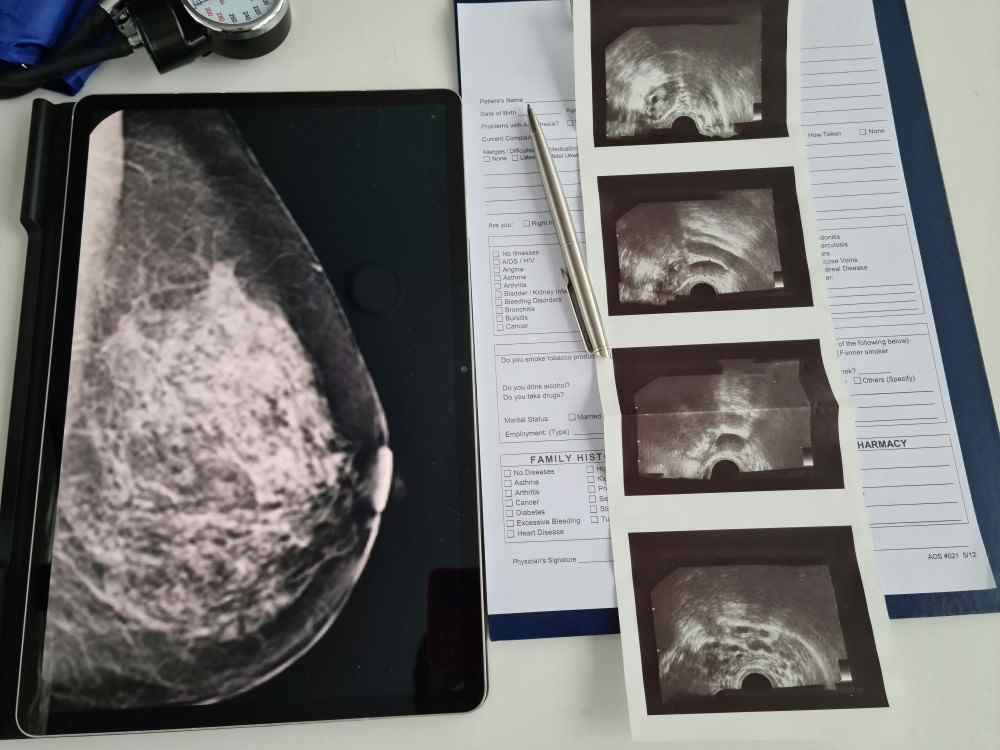

Les méthodes par imagerie : Radiologie mammographie

1- La mammographie reste l’examen de référence pour le dépistage du cancer du sein. Elle permet de détecter des anomalies avant même qu’elles ne soient palpables. Elle n’est pas parfaite, bien sûr. Chez les femmes aux seins denses, sa sensibilité diminue. Et parfois, elle génère des fausses alertes qui nécessitent des examens complémentaires.

2- L’échographie mammaire vient généralement compléter la mammographie. Elle est particulièrement utile dans certaines situations :

4- Scintigraphie : La scintigraphie est pratiquée lorsque le diagnostic du cancer du sein est tombé. Elle permet de rechercher des lésions cancéreuses à distance notamment des métastases osseuses.